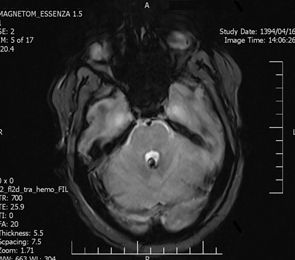

Background: Cavernous hemangiomas are common benign vascular malformations. Their existence in the intraventricular region is very rare. Case Reports: A 43-year old woman with an occipital headache was admitted to the emergency ward. Brain computed tomography scan showed mild hydrocephalus and multiple intraventricular isodense lesions. Imaging findings, especially of Gradient Resonance Echo imaging, were in favor of multiple intraventricular cavernous malformations. Conclusion: This is a rare presentation of multiple cavernous malformation as occipital headache without needing surgical intervention in this phase. Coexistence of periventricular plaques like Radiologically isolated syndrome of Multiple sclerosis is another unique aspect in this report. [GMJ.2017;6(1):61-65]